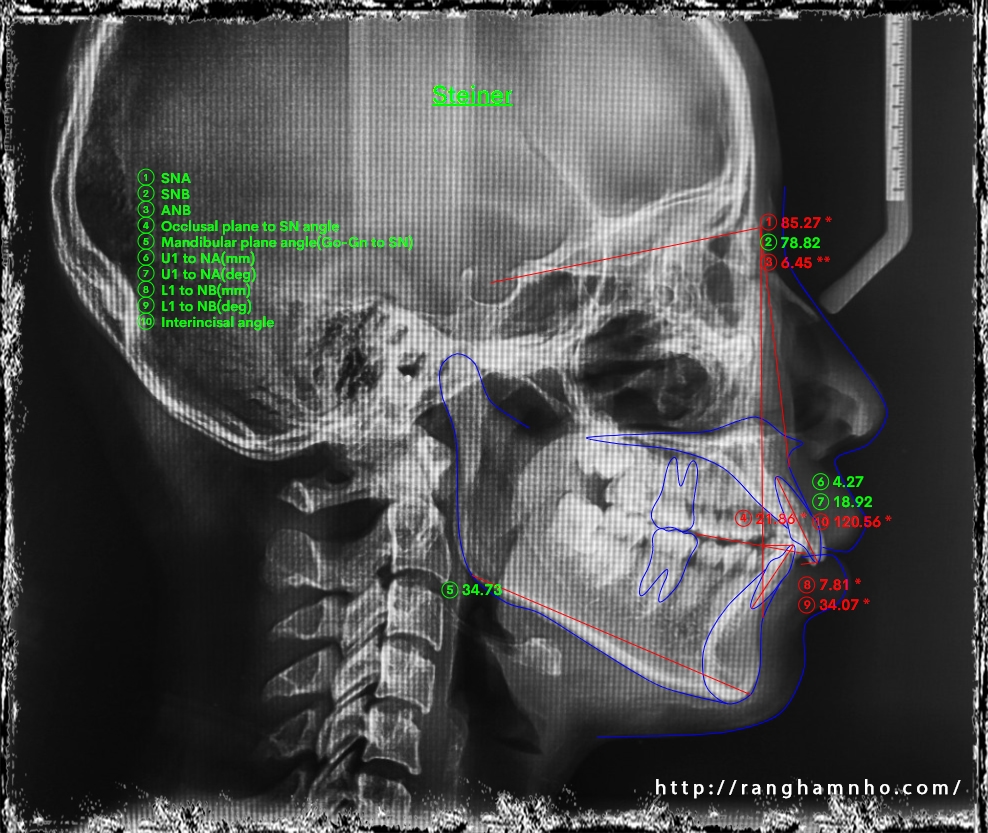

Chẩn đoán trước điều trị: sai khớp cắn hạng II, mặt hô, khớp cắn sâu. Chỉ định niềng răng nhổ 4 răng số 4 để kéo lùi nhóm răng cửa giảm hô tối đa. Có sử dụng neo chặn tuyệt đối bằng minivis chỉnh nha.